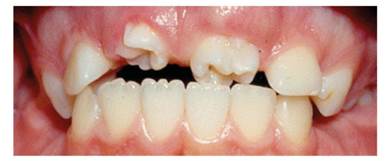

Figure 3, Figure 4, Figure 5 and Figure 6 show the clinical images and x-ray image of a 10-year-old male patient who consulted the Emergency Clinic of Universidad del Valle School of Dentistry. They show two large molariform teeth in the upper anterior region in between the lateral incisors. The radiograph shows that the upper right mesiodens has moved the right central incisor to the region of the lateral right, and the left upper mesiodens is blocking the eruption of the left central incisor.

Note the presence of two molariform mesiodens blocking eruption of the upper central incisors

In case 2, the molariform mesiodens were blocking the eruption of permanent incisors, agreeing with what has been reported in the literature,32)(33) affecting the room available for teeth in the upper anterior segment. In case 3, the conical mesiodens allowed the eruption of permanent central incisors with lateral displacement, as previously reported.2)(13